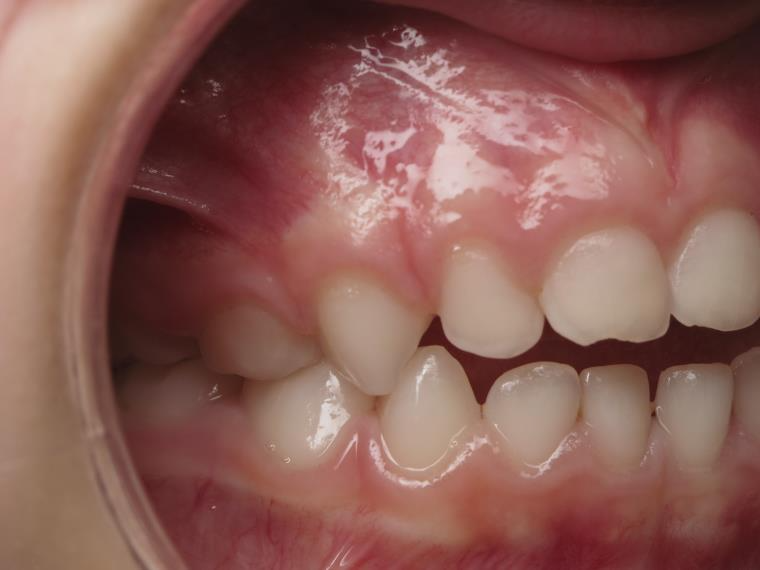

surveillance évolution de la dentition en cours

bilan début et en cours de traitement